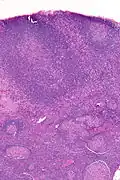

| Micrograph of a lymph node biopsy showing progressive transformation of germinal centres. H&E stain. | |

Microscopic appearance

PTGCs is characterized by:[1]

- follicular hyperplasia (many follicles),

- focally large germinal centres, with poorly demarcated germinal centre (GC)/mantle zone interfaces (as GCs infiltrated by mantle zone lymphocytes), and

- an expanded mantle zone.